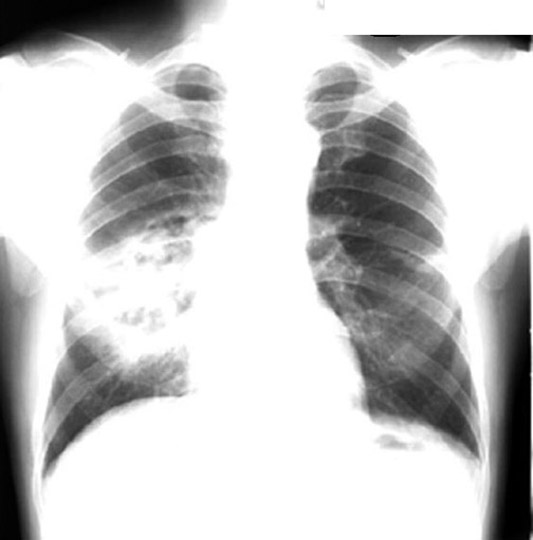

47 year old alcoholic presented with fever, cough and weight loss of 3 weeks duration.  History of 40 pack years of smoking.

Findings:

• Superior segment RLL dense pneumonia

• Note the progression  / Cavity / Complete clearance

• Necrotizing pneumonia

Aspiration Lung Abscess